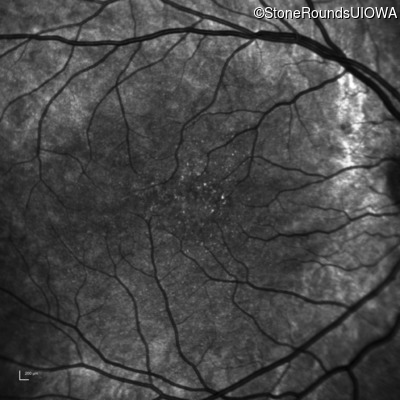

Infrared Fundus Photograph - Right - 10/16 sc

Exemplar